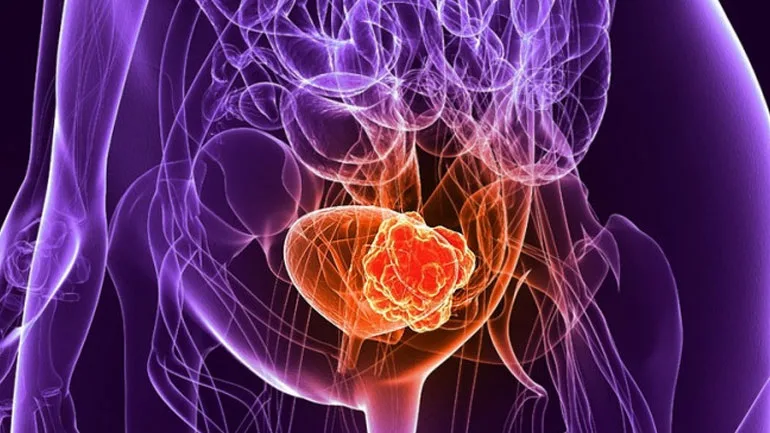

Αυξημένος ο κίνδυνος καρκίνου της ουροδόχου κύστης για τις γυναίκες με πρόωρη εμμηνόπαυση

Οι γυναίκες που έχουν εμμηνόπαυση πρόωρα, πριν από τα 45 τους, αντιμετωπίζουν αυξημένο κίνδυνο για καρκίνο της ουροδόχου κύστης, σύμφωνα με μια νέα διεθνή επιστημονική έρευνα. Ο κίνδυνος είναι μεγαλύτερος για όσες καπνίζουν επί χρόνια.

Ο συγκεκριμένος καρκίνος είναι ο έκτος συχνότερος στην Ευρώπη και είναι πιο κοινός στους άνδρες από ό,τι στις γυναίκες (περίπου τριπλάσιες οι διαγνώσεις σε άνδρες). Όμως, οι γυναίκες είναι πιθανότερο να εμφανίσουν προχωρημένο καρκίνο της ουροδόχου κύστης και έχουν μικρότερες πιθανότητες επιβίωσης σε σχέση με τους άνδρες (η θνησιμότητα στις γυναίκες είναι περίπου 40% μεγαλύτερη). Κάθε χρόνο περίπου 27.000 γυναίκες στην Ευρώπη και 19.000 στις ΗΠΑ διαγιγνώσκονται με τον εν λόγω καρκίνο.

Διαπιστώθηκε ότι εκείνες με εμμηνόπαυση πριν από την ηλικία των 45 ετών ήταν κατά μέσο όρο 45% πιθανότερο να εμφανίσουν καρκίνο της ουροδόχου κύστης, σε σχέση με όσες είχαν εμμηνόπαυση μετά τα 50. Ο κίνδυνος ήταν ακόμη μεγαλύτερος (53%) για τις καπνίστριες που είχαν πρόωρη εμμηνόπαυση.